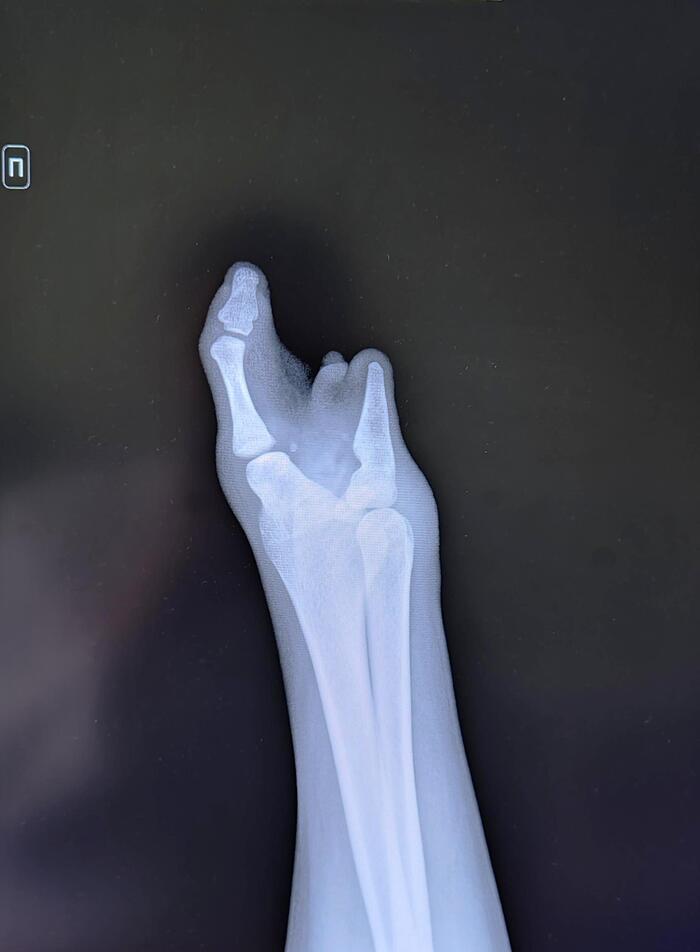

Врожденный порок развития кисти- симбрахидактилия

Симбрахидактилия – врожденная аномалия развития кисти, проявляющаяся множеством клинических признаков, включая брахидактилию, синдактилию и гипоплазию кисти. Фенотипические проявления симбрахидактилии очень вариабельны.

На рентгенограммах правой кисти в 2х проекциях: лучезапястный сустав, кости кисти-отсутствуют. Визуализируются дистальные эпифизы лучевой и локтевой костей, заканчивающиеся тремя фалангами.

Заключение: Врожденный порок развития правого предплечья и кисти-симбрахидактилия.